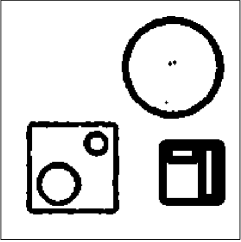

The data (see Figures 1 and 2) was generated in the diffusion model (1.2) using self-written (linear-basis) finite element code in MATLAB. For both examples, we took and used a uniform boundary condition . The simulated data were generated on a -grid and then down-sampled (by averaging) to to avoid inverse crime. After that, Gaussian noise with different intensities (standard deviations of and of the average signal value ) was added to the data.

Reconstruction results and error profiles at different noise levels can be seen in Figures 3 and 4. In both examples, the noise-free reconstructions are very accurate and contain mostly smoothing error. In the low-noise reconstructions, due to the fact that more regularization is necessary, some of the parameter variation is underestimated. In the high-noise examples, most detail in is lost since a lot of regularization is required to get reasonable results. The fine detail in can, however, still be recovered very accurately in both examples.